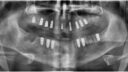

mir wurden Anfang Februar im OK 9 Implantate und im UK 6 Implantate gesetzt. Vor 3 Wochen haben bei sich mir unten rechts am mittleren Implantat Schmerzen entwickelt. Erst fingen diese ganz leicht an und nun werden sie immer stärker.

Ich war bereits bei meinem Zahnarzt gewesen, dieser meinte, dass alles gut aussieht und das normal wäre. Für mich fühlt es sich allerdings alles andere als normal an. Der Schmerz kommt von Innen am Implantat.

Zuzufügen ist auch, dass ich vorher an dem Zahn eine Wurzelbehandlung bekommen hatte und ich bis zum Ziehen des Zahnes dort schmerzen hatte. Mir wurde dort ein Sofortimplantat eingesetzt.

Hätte jemand noch eine Idee woran das liegen kann oder sieht jemand eventuell doch etwas auf dem Röntgenbild?Vielen Dann für eure Hilfe!